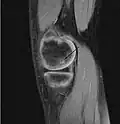

Magnetic resonance imaging (MRI) is useful for staging OCD lesions, evaluating the integrity of the joint surface, and distinguishing normal variants of bone formation from OCD by showing bone and cartilage edema in the area of the irregularity. MRI provides information regarding features of the articular cartilage and bone under the cartilage, including edema, fractures, fluid interfaces, articular surface integrity, and fragment displacement.[37][38] A low T1 and high T2 signal at the fragment interface is seen in active lesions. This indicates an unstable lesion or recent microfractures.[30] While MRI and arthroscopy have a close correlation, X-ray films tend to be less inductive of similar MRI results.[38]

Sagittal MRI: Linear low T1 signal at the articular surfaces of the lateral aspects of the medial condyle of the femur confirms the presence of OCD. -